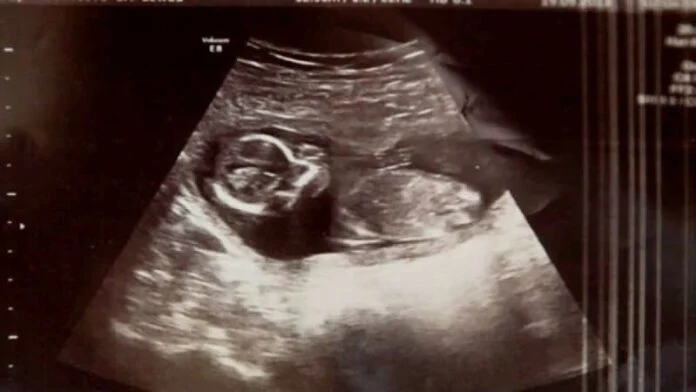

Οι γιατροί στο νοσοκομείο ελέγχουν με υπέρηχο την κοιλιά της Μισέλ για μια τελευταία φορά πριν προχωρήσουν σε ξύσμα της μήτρας και βρίσκουν το αλάνθαστο κτύπο της καρδιάς ενός εμβρύου! Η Μισέλ είναι έγκυος, παρά την αποβολή και την άμβλωση. Αποδεικνύεται ότι ήταν αρχικά έγκυος με δίδυμα, αλλά μόνο ο ένας απεβλήθη. Πώς το δεύτερο μωρό κατάφερε να επιβιώσει, ακόμα και οι γιατροί δεν μπορούν να εξηγήσουν!

“Ο γιατρός βγήκε και επέστρεψε πάλι με ένα μεγαλύτερο σε ηλικία συνάδελφο, ο οποίος επανέλαβε τη διαδικασία και, στη συνέχεια, είπε, “Δεν θα μας πιστέψετε, αλλά έχουμε έναν κτύπο καρδιάς.” Αυτό ήταν το καλύτερο συναίσθημα που είχα ποτέ , λέει η Μισέλ. Στο τέλος, το μωρό Μέγκαν γεννήθηκε υγιέστατο και άφησε άναυδους τους γιατρούς και τους γονείς.

Δεν είναι σαφές, αν υπήρξε ποτέ μια παρόμοια περίπτωση, όπως της Μέγκαν. Σήμερα το μωρό είναι 18 μηνών και είναι απολύτως υγιής. Ακόμη και τα αδέλφια της 4 και 2 χρονών είναι ευτυχισμένα που την έχουν στη ζωή τους. Είναι επίσης άγνωστο το πώς το έμβρυο αγνοήθηκε κατά τη διάρκεια των προηγούμενων εξετάσεων. Οι γιατροί λένε ότι η Μέγκαν ήταν κρυμμένη από τον υπερήχο από το αίμα και άλλα υγρά της αποβολής.